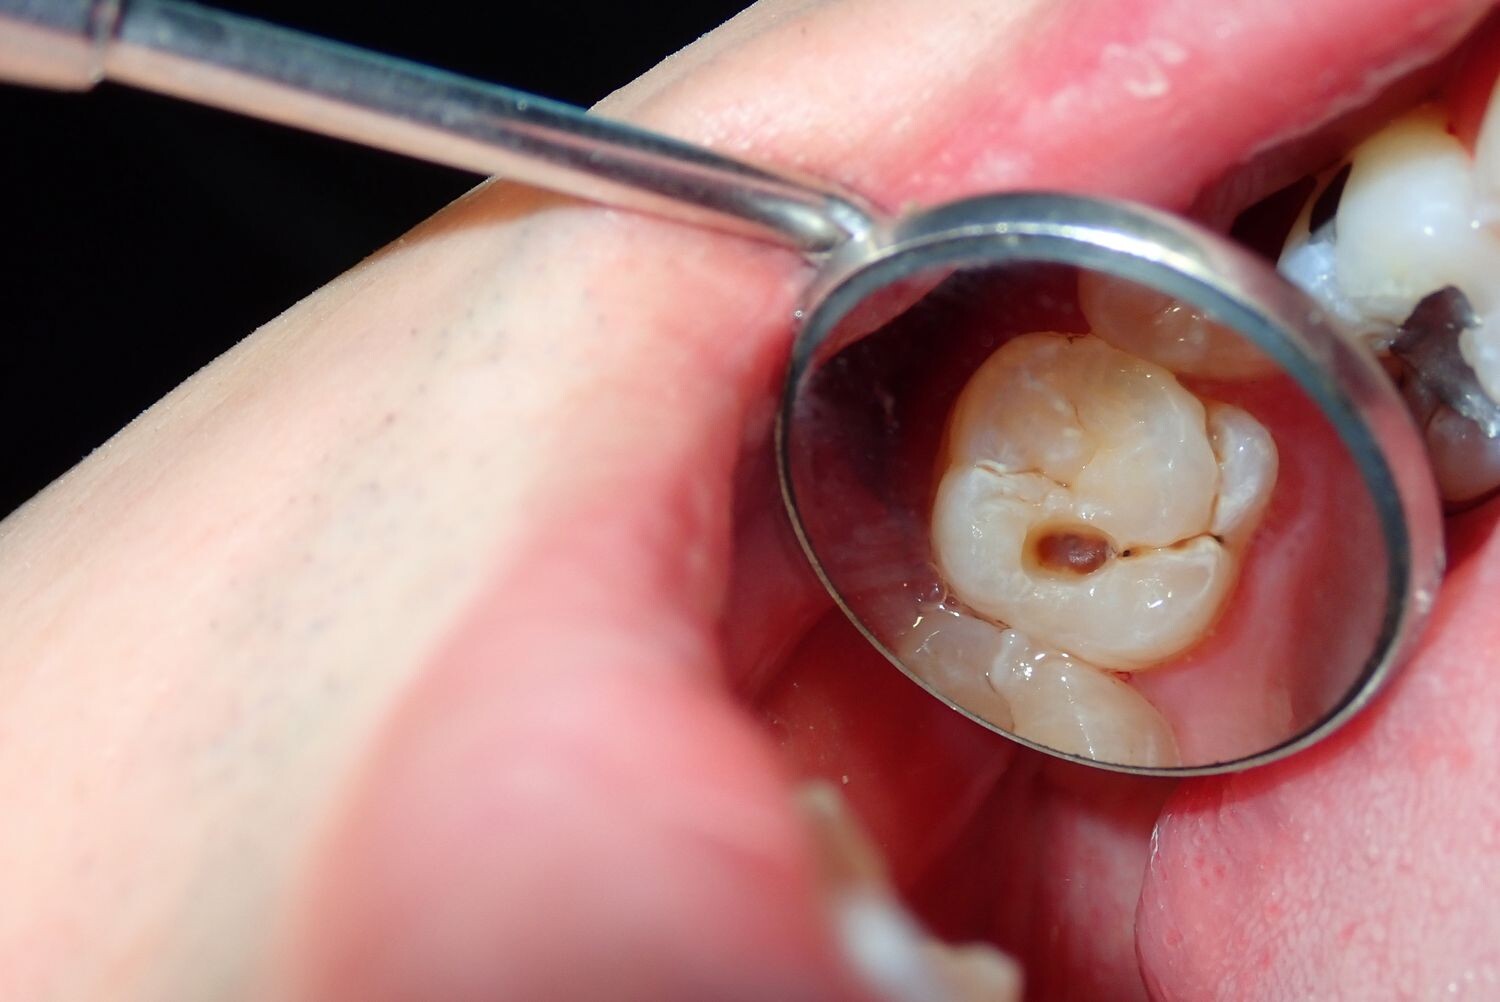

Cavities are pretty common. As the National Institutes of Health points out, the only condition more common than a cavity is the common cold. If you've never experienced tooth decay, you might wonder, "What does a cavity feel like?" The answer depends on the stage of the cavity and what foods you eat. Some foods, such as sweets, might trigger the pain of a cavity more than others.

What does a cavity feel like? In the earliest stages, the answer might be nothing. There are no nerves in your tooth enamel, so when the decay is in that layer, you likely won't feel a thing. Once the decay has progressed enough to reach the softer tissues inside the tooth, where the dentin and nerves are, you might notice signs of a cavity. Your teeth might feel sensitive and you could feel some pain, especially after eating sweets, hot foods or cold foods. The pain can be fairly mild or sharp and intense. Some people with cavities also feel pain when biting down.

Depending on the size of the cavity, you may be able to see evidence of it in your mouth. Cavities sometimes create visible holes in the teeth. They can also create stains that are black, brown or white on the surface of the tooth.